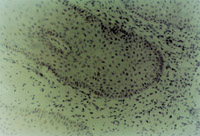

經(jīng)MEBT/MEBO治療10天,創(chuàng)面組織切片可見(jiàn)表皮棘層棘細(xì)胞出現(xiàn)并有橋粒連接(圖5-3-14~5-3-15)。顆粒層顆粒細(xì)胞出現(xiàn)。在基底細(xì)胞層可見(jiàn)黑色素小體(圖5-3-6~5-3-17)。并可見(jiàn)小血管周圍的吞噬細(xì)胞有吞噬現(xiàn)象(圖5-3-18),說(shuō)明其功能也已經(jīng)在恢復(fù)。

5-3-14 MEBT/MEBO治療20天,4個(gè)棘細(xì)胞的橋粒連接   TEM×3500

5-3-15 橋粒結(jié)構(gòu) TEM×20000